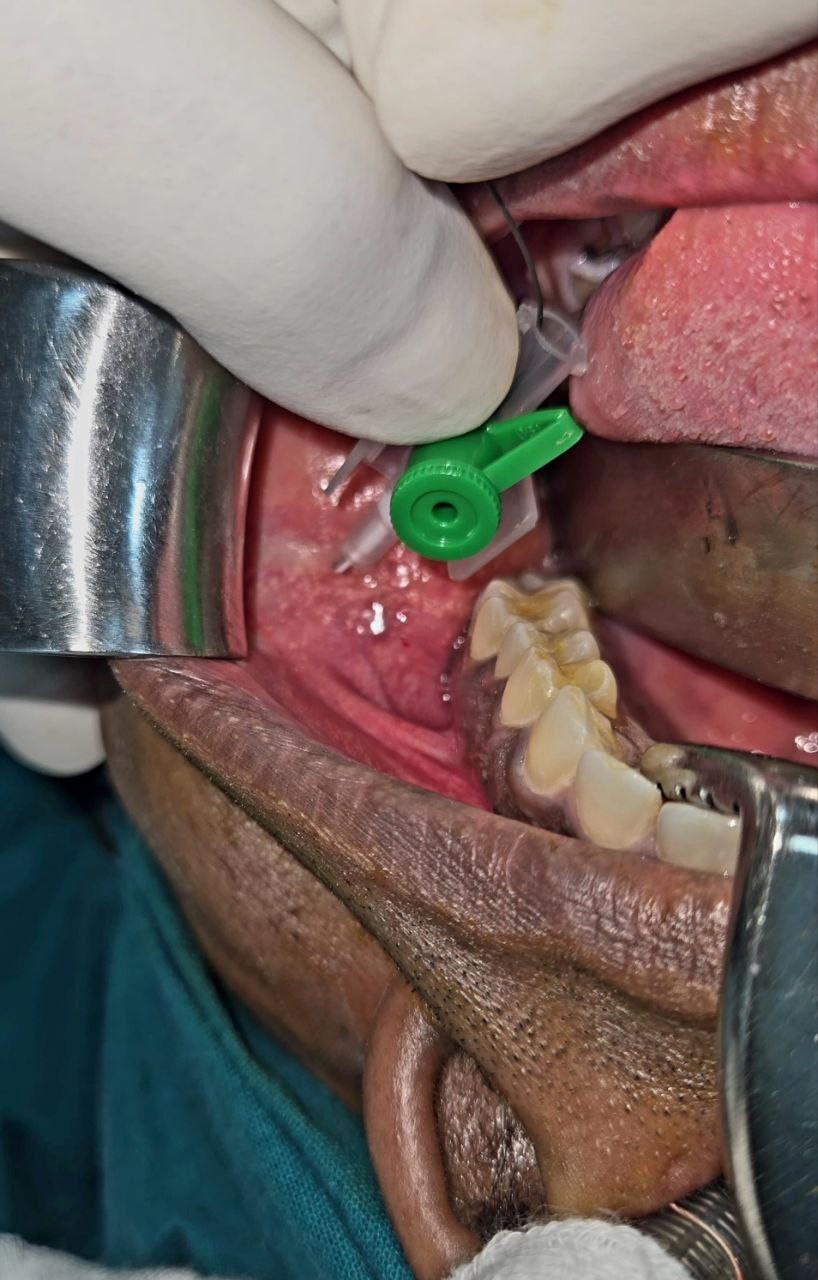

- The Stensen’s duct orifice was identified intraorally opposite the upper second molar.

- A guidewire was gently introduced into the duct, and a 3 Fr DJ stent was advanced over it to delineate and protect the duct throughout the procedure.

Drain: None. - A horizontal mucosal incision was made in the left upper vestibule, parallel to the course of the duct.

- Peritumoral tumescence with saline-adrenaline solution was injected transcutaneously to facilitate atraumatic dissection.

- Blunt dissection through the buccinator fibers exposed the parotid capsule.